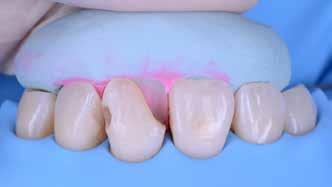

A cikkünkben bemutatásra kerülő eset ellátása során preparációt héjak készre vitele során a platinafólia technikát alkalmaztuk.

preparációt nem igénylő héjak készítése mellett döntöttünk. A alkalmaztuk. Annak ellenére, hogy az elkészítésre kerülő héjak rendjelentős törésveszéllyel állunk szemben, összességében mégis

javasoljuk e módszer alkalmazását.

A platinafólia technikát 1896 óta alkalmazzák. Napjainkra az eredeti eljárás már kismértékben módosításra került, de lényegében ugyanazzal a módszerrel történik a platinafóliára készülő koronák és héjak elkészítése. A minimál invazív fogászat egyre szélesebb körben történő elterjedésének köszönhetően ez az eljárás a reneszánszát éli. A pácienseink egyre gyakrabban szeretnék a fogaik alaki, színi vagy helyzeti rendellenességeit a lehető legkisebb saját foganyagveszteség árán korrigáltatni. Az eljárás során 0,025 mm vastag 99,9%-os tisztaságú platinafólia kerül alkalmazásra. Amennyiben a megfelelő technikai háttér és a beavatkozások elvégzéséhez szükséges elméleti és gyakorlati szaktudás is rendelkezésünkre áll, akkor semmi sem állhat az utunkba a pácienseink új mosolyának kialakítása során.

A módszer első lépéseként a gipszből kiöntött csonkokat platinafóliával borítjuk (5. ábra). Az adaptálását követően a felhelyezett fóliát óvatosan eltávolítjuk, felhevítjük, majd ismét visszahelyezzük a csonkokra. Ezt követően történik meg az első kerámiaréteg felvitele (Waschbrand). Az első égetés során csupán egy nagyon vékony réteg kerámia kerül a fólia felszínére (6. ábra). Amikor az égetést követően ezt

a kezdetleges kerámiavázat visszahelyezzük a csonkokra, a kerámia anyagában vékony repedések alakulnak ki. A végleges restaurátum elkészítéséhez szükséges kerámia „köpeny” ekkor áll készen a további kerámiarétegek felvitelére és kiégetésére (opaker réteg, dentin- és zománcmassza felvitele) (7-10. ábra). A készülő fogpótlás végső formai megjelenése rétegenként kerül kialakításra.

A cikkünkben bemutatásra kerülő eset ellátása során preparációt nem igénylő héjak készítése mellett döntöttünk. A héjak készre vitele során a platinafólia technikát alkalmaztuk. Annak ellenére, hogy az elkészítésre kerülő héjak rendkívül vékonyak, és ezáltal a végleges rögzítésük előtt jelentős törésveszéllyel állunk szemben, összességében mégis olyan minimál invazív kezelési eljárásnak számítanak, amely segítségével kifogástalan esztétikai eredményeket lehet elérni. A fent leírtak alapján bátran javasoljuk e módszer alkalmazását.